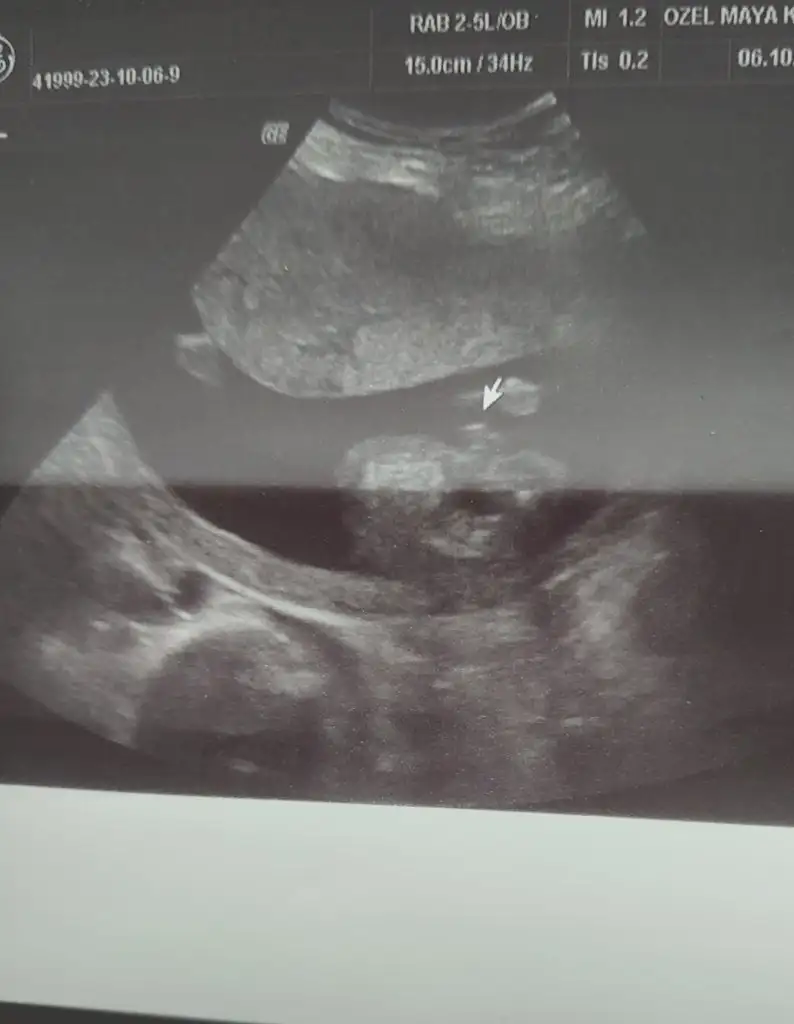

Merhaba arkadaşlar banada bakabilir misiniz? 12+3 kız dedi doktorum 17. erkek dedi. Yanılmış olabilir mi? Kız hissediyorum hep:) 12 ve 17 haftaya ait görüntüleri